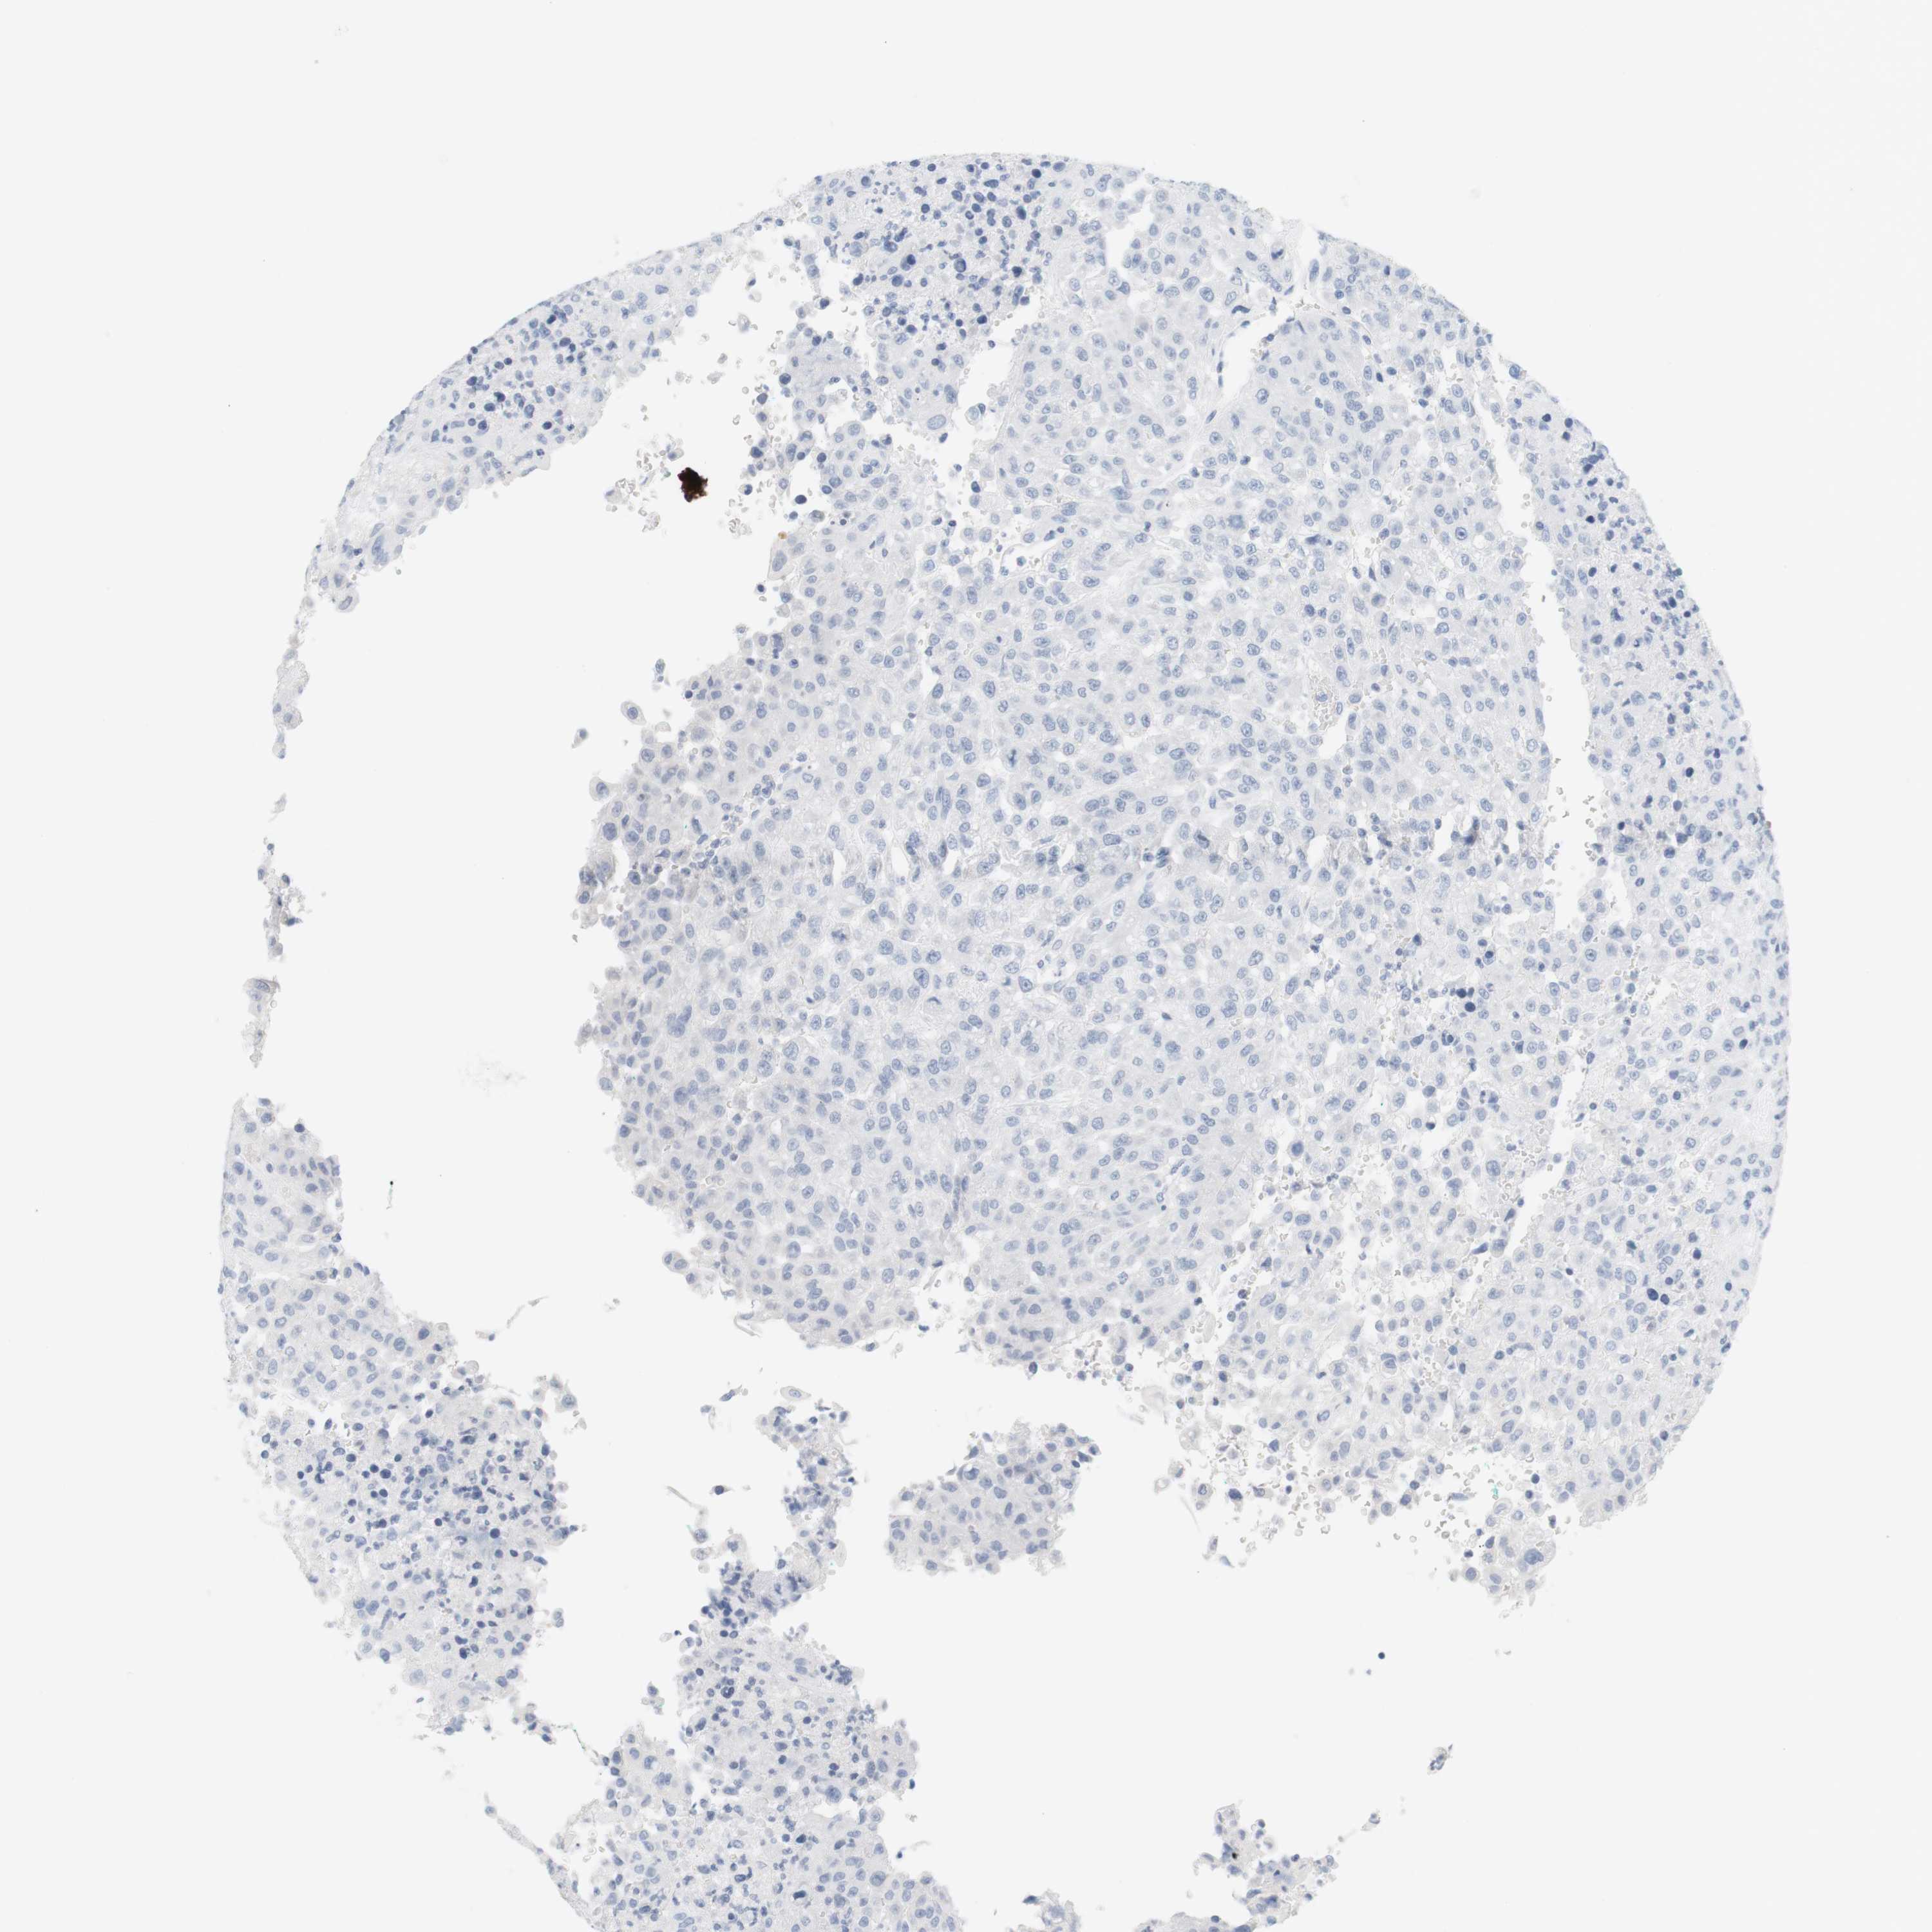

UROTHELIAL CANCER - Protein expressioni

A mouse-over function shows sample information and annotation data. Click on an image to view it in a full screen mode. Samples can be filtered based on level of antibody staining by selecting one or several of the following categories: high, medium, low and not detected. The assay and annotation is described here.

Note that samples used for immunohistochemistry by the Human Protein Atlas do not correspond to samples in the TCGA dataset.

Antibody stainingi

Antibody staining in the annotated cell types in the current human tissue is reported as not detected, low, medium, or high, based on conventional immunohistochemistry profiling in selected tissues. This score is based on the combination of the staining intensity and fraction of stained cells.

Each image is clickable and will lead to virtual microscopy that enables deeper exploration of all samples and also displays staining intensity scores, fraction scores and subcellular localization as well as patient and tissue information for each sample.

Antibody HPA014509

Staining

High

Medium

Low

Not detected

Intensity

Strong

Moderate

Weak

Negative

Quantity

>75%

75%-25%

<25%

None

Location

Nuclear

Cytoplasmic/membranous

Cytoplasmic/membranous,nuclear

Urothelial carcinoma, Low grade

Urothelial carcinoma, High grade